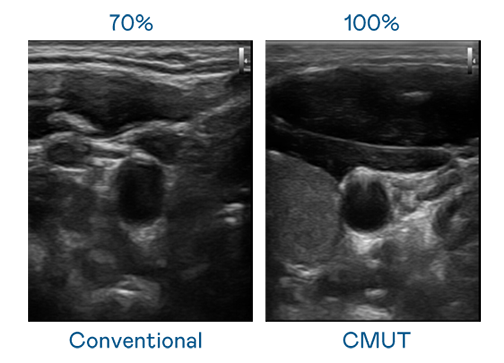

CMUT 技术是一种用电容式微机电元件来产生超音波讯号的技术。与传统 PZT 压电式技术相比,CMUT 频宽增加 30%,更宽频的超音波讯号让影像解析度大幅提升,是实现高影像品质医疗超音波扫描、促进精准医疗发展的关键技术。

超音波影像的解析度高低,首先取决于探头能发出的讯号频宽。DB旗舰 CMUT 可提供高清晰的超音波讯号,提供高频宽、高灵敏度、影像纹理细节更高的超音波影像,协助医护人员缩短影像判读时间及利用精准的医疗影像进行诊断。